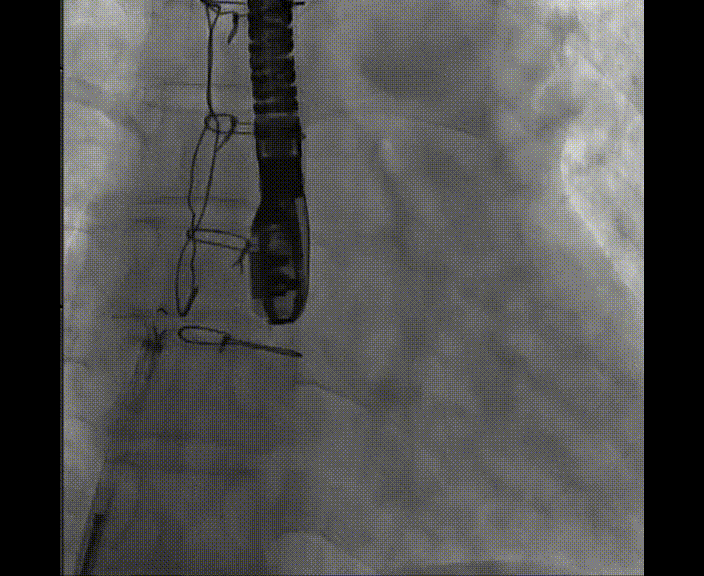

术中首先在局麻下穿刺股动脉、股静脉,完成心导管检查评估后转为全麻,在食道超声引导下穿刺房间隔,穿刺成功后将加硬导丝送入左上肺静脉建立轨道,根据患者病情行球囊预扩张后植入6mm孔径房间隔造孔支架,经透视及食道超声评估支架左右盘展开良好,夹持于房间隔两侧,固定稳定、位置良好,食道彩超显示房水平右向左为主分流,分流孔直径符合预期大小,心导管检查评估达到预期效果,释放造孔支架。术后12h患者下床活动,恢复顺利,拟于近日完善术后评估后出院。

图1.球囊预扩